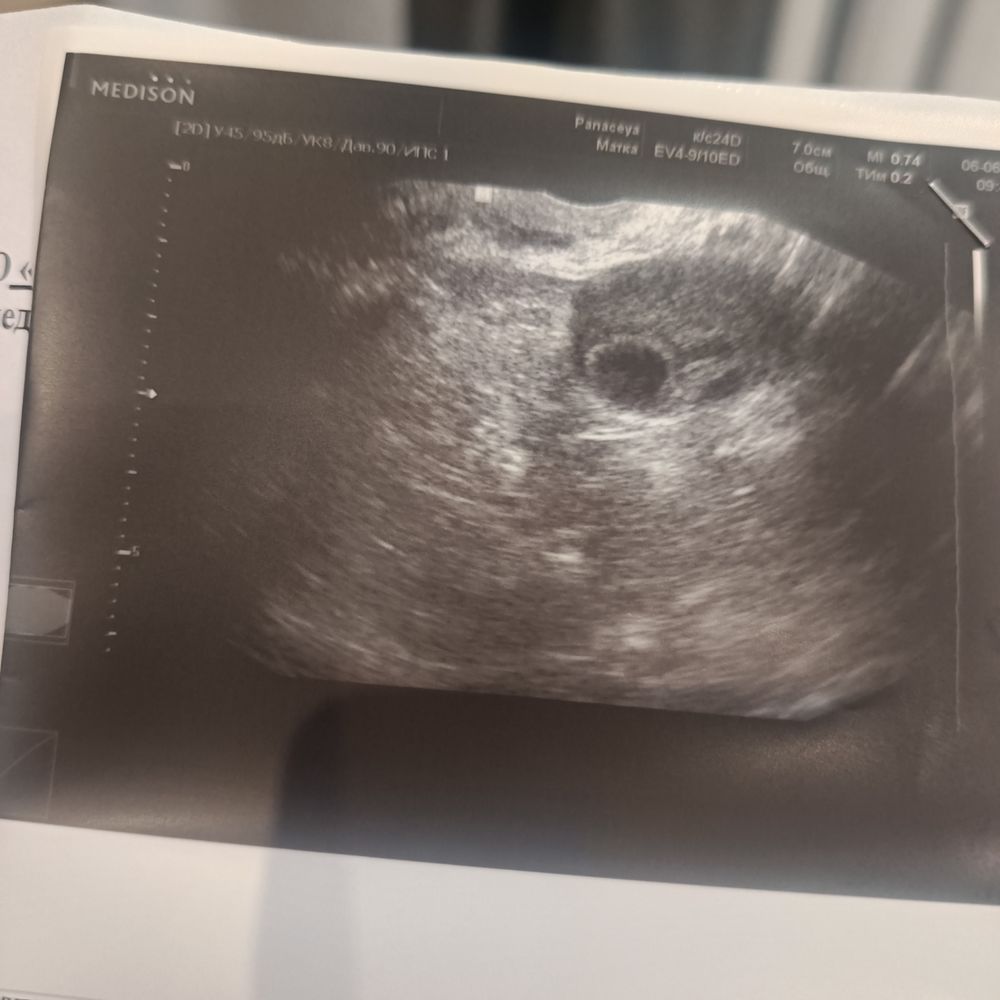

Просто сегодня ходила на УЗИ 17 дц .нашли жёлтое тело но размер не указали и сказала в принципе не влияет размер .была раньше поздняя овуляция сейчас похудела на 14 дц стало вот думаю применять ли дюф или урож .на 22 день цикла прогик был 5.18

Я ходила на 5 ДПО, жёлтое тело было 12 мм

Я расстроилась, потому что маленькое

Но врач сказала, главное что оно есть и размер не влияет

Надо смотреть, чтобы само количество гормона укладывалось в референсный интервал